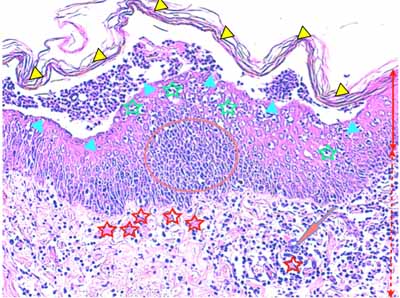

Photo 8 (Hémalun Eosine X 40) : L’épiderme est parsemé de vésiculo-pustules sous-cornées,

extensives, planes, dont le toit, composé de fines lamelles de kératine orthokératosique, est fragile.

Le derme montre un infiltrat de topographie péri-vasculaire.

Le patron lésionnel est celui d’une dermatite psutuleuse sous-cornée périvasculaire.

Légendes de la Photo 8 :

- Pointe de flèche turquoise : pustule intra-épidermique sous-cornée

- Flèche orange : infiltrat dermique de topographie péri-vasculaire

- Étoiles rouges pleines : vaisseaux sanguins

- Étoiles rouges vides : follicules pileux